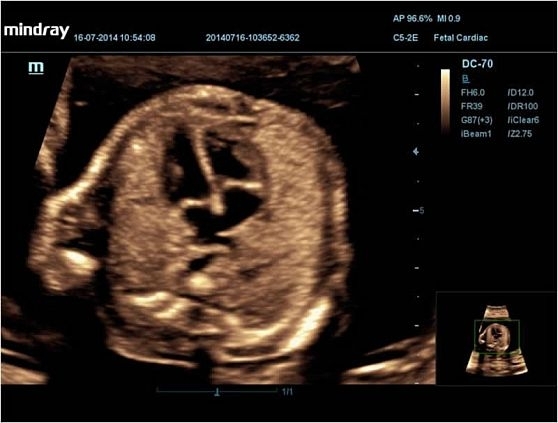

• Поддержка 3D/4D-визуализации для трёхмерного сканирования в реальном времени, особенно полезного в акушерстве и гинекологии.

• STIC — исследование сердца плода в серошкальном и ЦДК-режимах, требуется модуль 4D/TEE;

Изображения

Универсальные, Кардиологические, Гинекологические, Педиатрические, 3D/4D акушерство